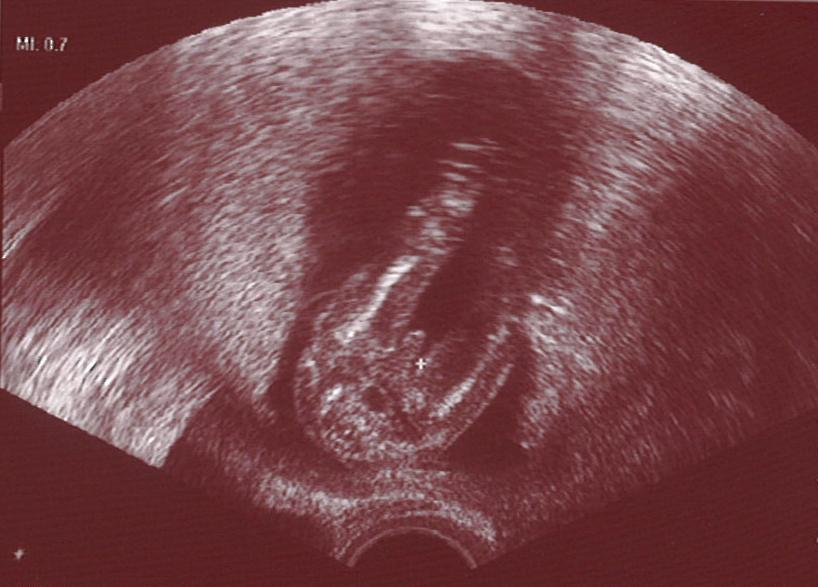

Katz-LE, das ist das geilste US-Bild, das ich bis jetzt gesehen hab (sorry für die Ausdrucksweise

) Was für eine Perspektive, ich lach' mich weg!!

Schön, dass es Dir gut geht und gratuliere zum Söhnchen!!